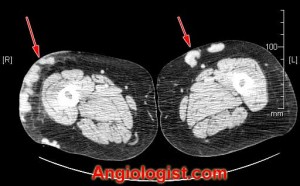

Other, less commonly utilized imaging studies that may demonstrate varicose veins include plain radiographs and CT scan imaging, as shown in the following pictures: